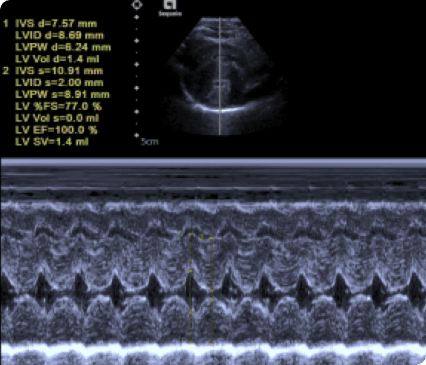

최고사양의 Siemens Sequoia 초음파 장비를 갖추고 있습니다.

일산시티동물의료센터는 최신 고해상도 초음파 장비를 통해 세밀하게 심장을 정밀하게 분석하여 심장질환을 진단합니다.